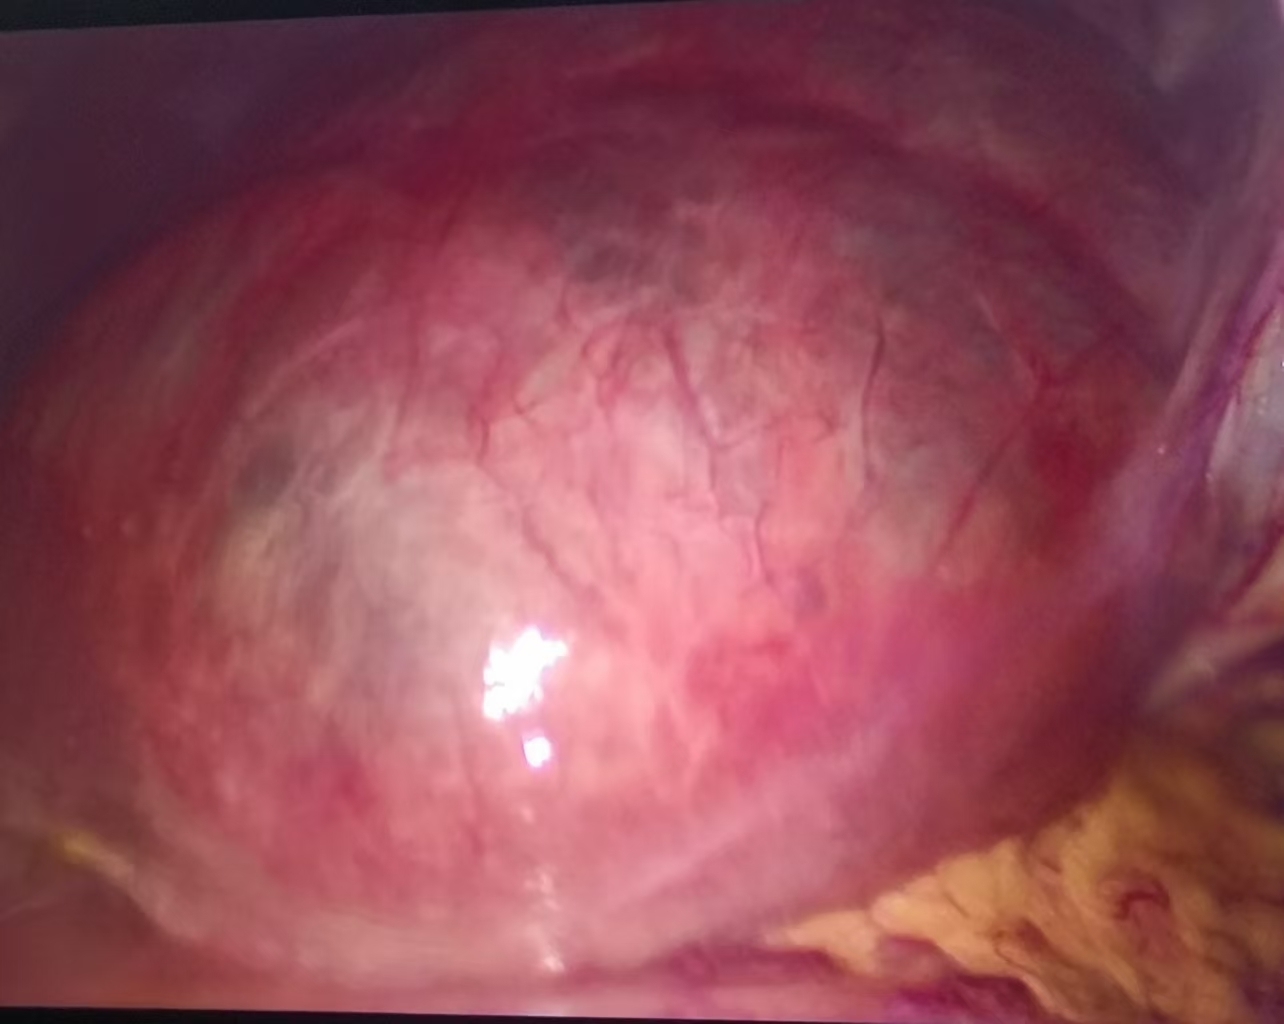

4. 手術治療:對于癥狀嚴重或囊腫較大的患者,需要行腹腔鏡肝囊腫開窗術。